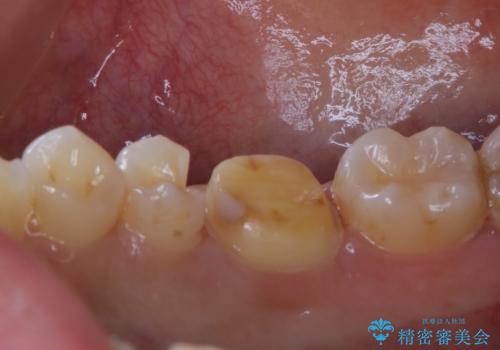

- 銀歯のやり替えをご希望された患者様です。手前の歯にもプラスチックと歯の間に虫歯が出来ていたため、両方とも適合の良いセラミックで補綴しました。

- セラミックインレー7.7万円・仮歯1.1万円・フルジルコニアクラウン7.7万円(税込)費用は治療当時の料金となります